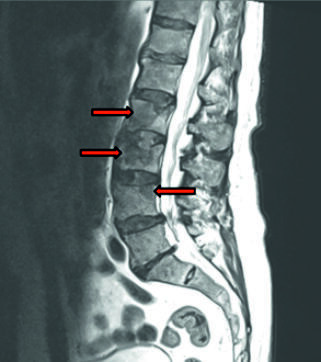

Lumbar spinal stenosis (LSS) is a common degenerative condition in older adults, leading to chronic low back pain, neurogenic claudication, reduced functional capacity, and impaired quality of life. It most frequently affects the L4/L5 and L5/S1 levels. Surgical intervention improves patient outcomes when conservative treatment fails. Coexisting conditions, such as prostate cancer with spinal metastases, increase the risk of fractures and bleeding. Refusal of blood transfusions by Jehovah’s Witnesses requires comprehensive patient blood management (PBM), including preoperative optimization, meticulous intraoperative hemostasis, and postoperative support. A 72-year-old man with chronic low back pain, neurogenic claudication, and progressive neurological deficits, with a history of prostate cancer and complete refusal of blood transfusions, presented for treatment. Magnetic resonance imaging (MRI) revealed critical stenosis at L4/L5 and degenerative changes at L2–L4. Conservative therapy was ineffective. The patient underwent transforaminal lumbar interbody fusion (TLIF) with pedicle screw fixation and a biopsy of L3. Recovery was uneventful, neurological deficits resolved, and follow-up MRI confirmed adequate decompression of neural structures. Histopathology demonstrated prostate cancer metastases. The procedure provided decompression and spinal